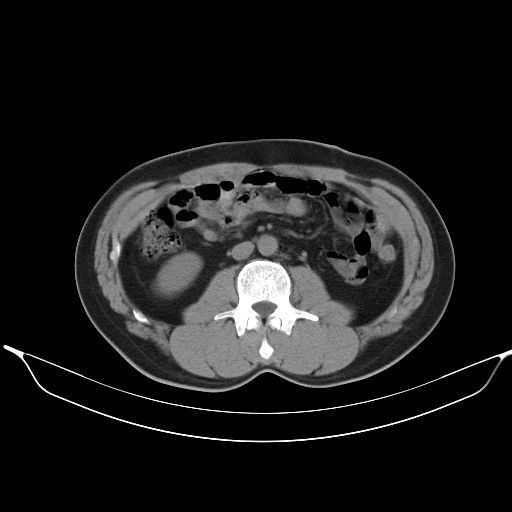

标题: CT25490:男,40岁,体检发现;无其它不适。 [打印本页]

标题: CT25490:男,40岁,体检发现;无其它不适。

转移性肺肿瘤不排除,建议结合相关检查考虑

1、均为转移,原发灶不在肺内。2、肺癌肺转移。